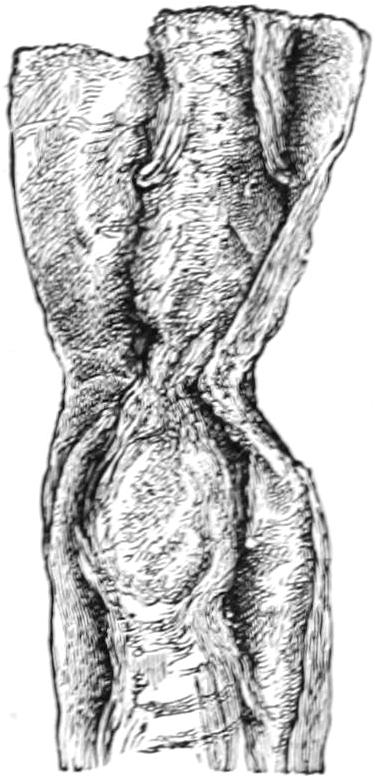

Fig. 1

Congenital hypertrophy: gigantism of both lower extremities. (Case of Dr. Graefe [Sandusky].)